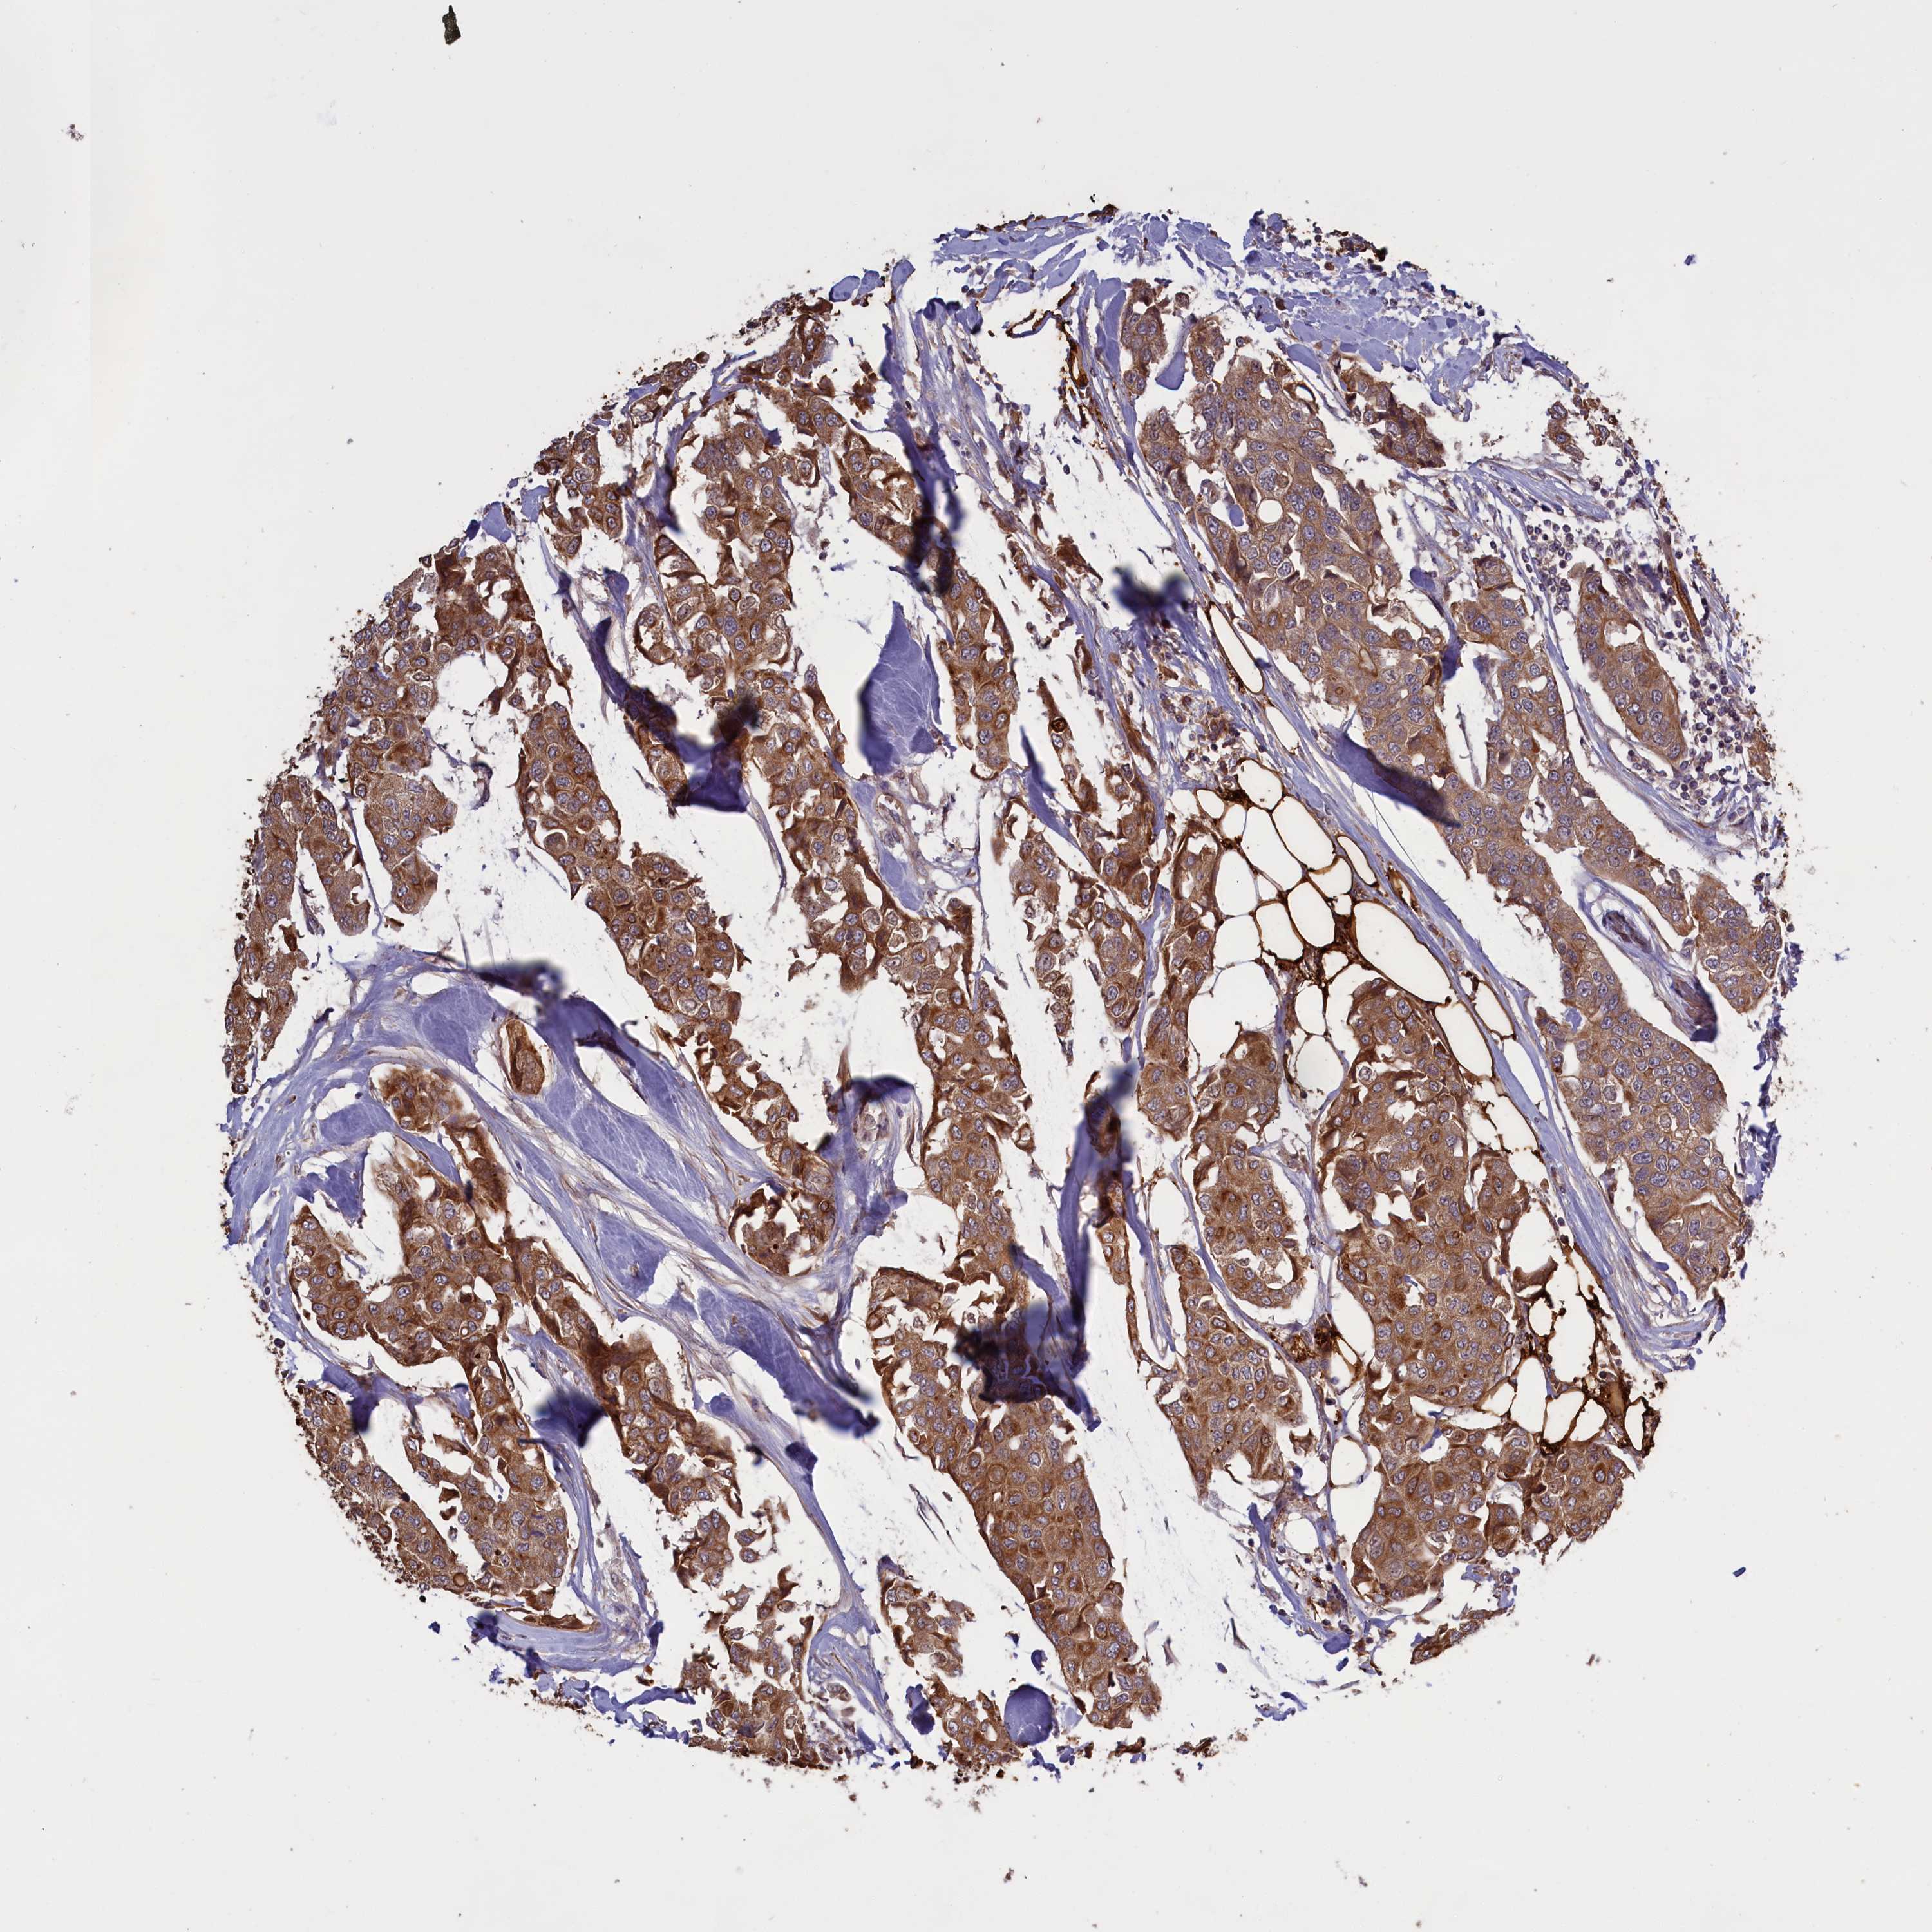

CANCER BREAST CANCER Show tissue menu

BRCA TCGA BRCA VALIDATION PROTEIN EXPRESSION